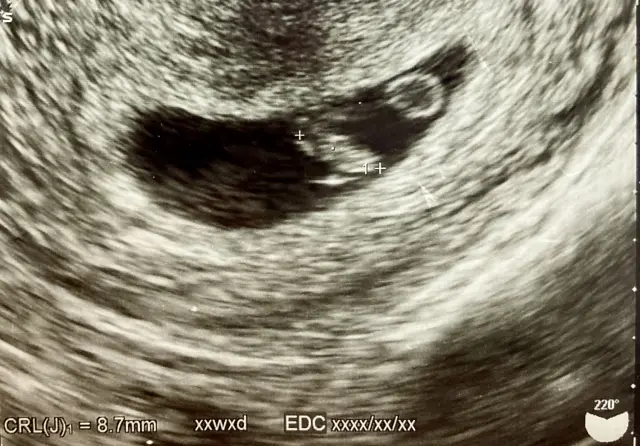

妊娠7週のエコー8.7mmまだ大きくなってきています。